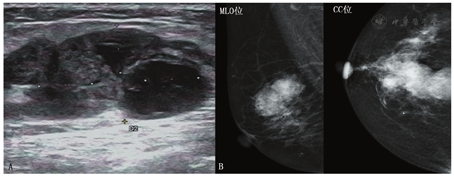

B超示:右侧乳腺12点低回声肿块,边界欠清(BI-RADS分类:4c类)。钼靶示:右侧乳腺内团块状高密度影,边缘毛糙。妇科B超示:子宫、双侧附件未见异常(病例19图1)。

注:B超示右侧乳内低回声肿块,边界欠清(A);钼靶示右侧乳腺内团块状高密度影,边缘毛糙(B)